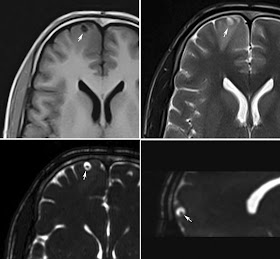

MRI Brain of 26 year old male presented with seizures, T1 image showing well defined small hypointense lesion in the right frontal cortical region, which is showing hyperintense on T2 image. CISS 3D - heavily weighted T2 images (bottom row) showing fluid intensity lesion with small hypointense focus. The findings are consistent with neurocysticercosis.